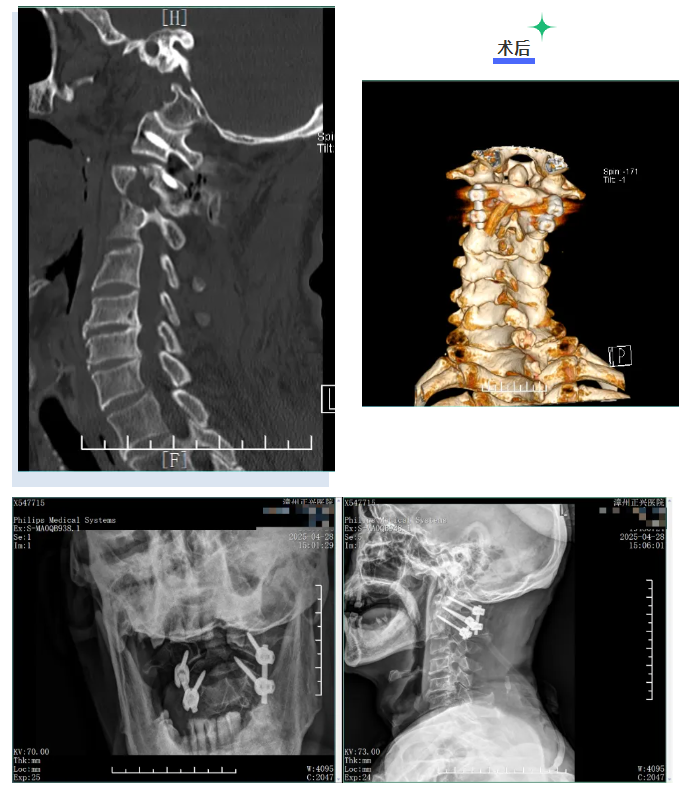

在手术室麻醉科医护人员的密切配合下,康两期主任医师团队为患者施行寰枢椎骨折后路切开复位内固定术,术中见枢椎齿状突基底部骨折,骨折端稍移位,予复位及椎弓根钉固定,骨折端位置良好,颈椎高度恢复正常。

历经 2 小时,康两期主任凭借精湛的技术和丰富的经验,顺利完成这例高难度的手术,术中出血极少,术后患者恢复良好,术后影像显示骨折部位已复位,固定可靠。

经骨科中心团队综合评估后,由康两期主任医师主刀为患者顺利完成后路颈1、2骨折切开复位椎弓根钉内固定术+右桡骨远端骨折切开复位钢板内固定术,手术顺利,术后患者清醒,安返病房。后续张阿姨恢复良好。